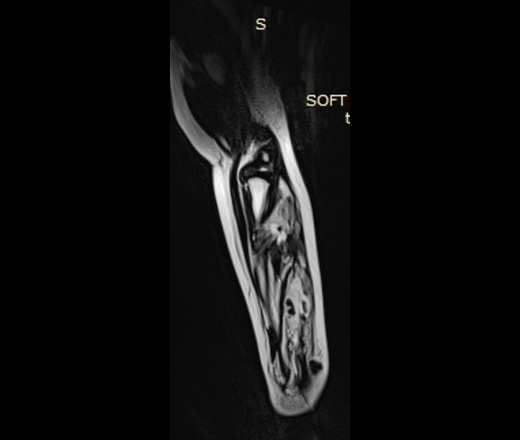

При контролях в динамике - мягкотканный компонент с наличием округлых теней.

УЗИ - мягкотканный компонент с наличием кровотока.

МРТ - гемангиома мягких тканей.

Округлые плотные тени - флеболиты.